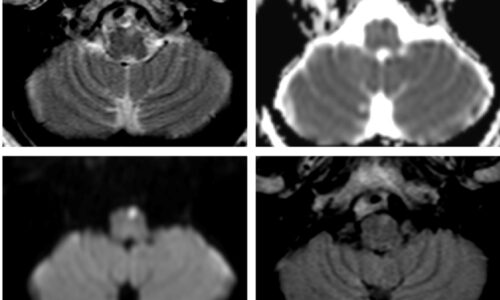

Lesiones del tronco encefálico: correlación anatómico-imagenológica en una serie de casos

Bajada Este artículo ilustra patrones representativos de lesiones mesencefálicas, pontinas y bulbares, mediante una serie de casos con énfasis en la correlación anatómico-imagenológica (…).